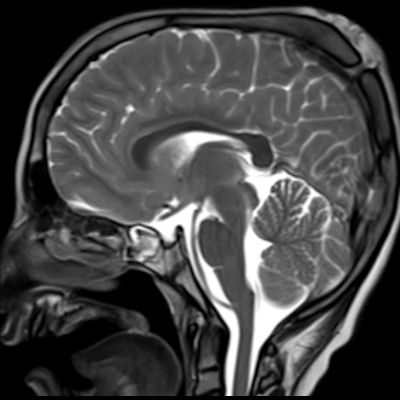

1. A) Kontrastlı FLAIR aksiyel görüntüde ve sagital T2A görüntüde vertekste orta hatta cilt altında dilate tortiyoze vasküler kollateraller (oklar). Paryetal kemikte orta hatta defekt (ok) ve defekt ile ilişkili vasküler yapıların cilt altı yumuşak dokulara uzanımı izlenmektedir.